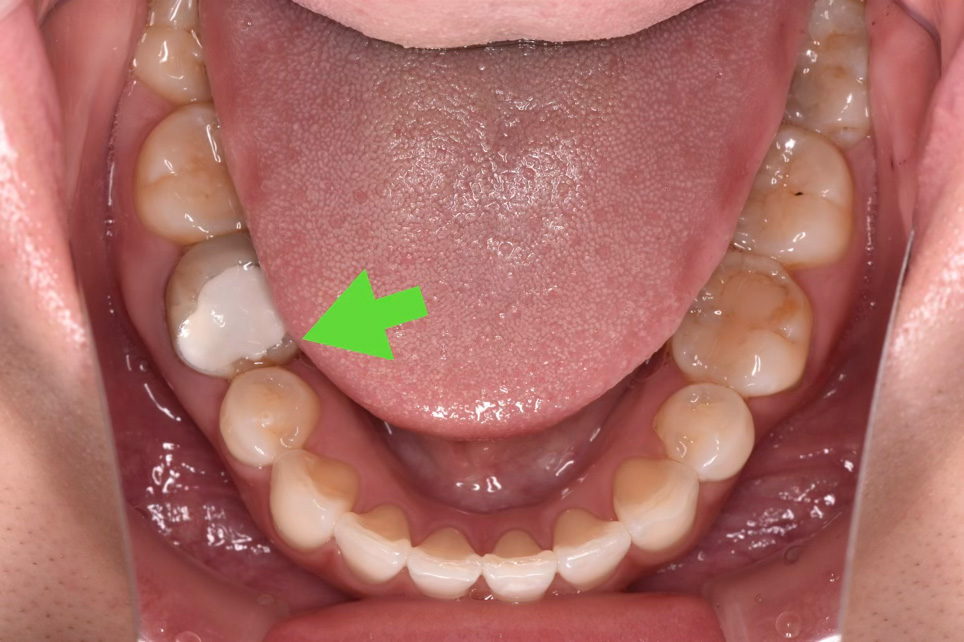

緑の矢印部(←)が今回治療を行った右下の第一大臼歯です。白い部分は仮の詰め物がされておりました。仮の詰め物の範囲からも、大部分の歯がなくなってしまっていることがわかります。